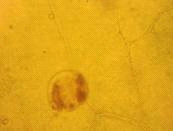

.1.2 Микроскопический анализ

При микроскопическом исследовании препаратов

листа с поверхности обнаруживаются простые многоклеточные волоски с

бородавчатой кутикулой и головчатые волоски с одноклеточной ножкой и

обратнояйцевидной одноклеточной головкой. Устьица диацитные. По поверхности в

углублениях видны многочисленные эфирномасличные железки (рис. 4). Эпидермис

извилистостенный (рис. 3). [1]

Рис. 3. Извилистые стенки эпидермиса

Рис. 4. Эфирномасличная железка